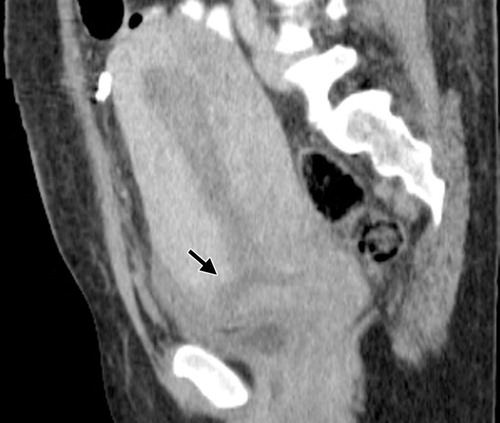

Figure 10: Sagittal portal phase reformatted CT image following a normal caesarean section reveals a low transverse discontinuity (arrow) at the incision site in the anterior portion of the lower uterine segment. (Reprinted with permission) [5].